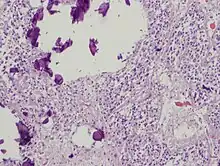

Pineal gland parenchyma with calcifications

The pineal body in humans consists of a lobular parenchyma of pinealocytes surrounded by connective tissue spaces. The gland's surface is covered by a pial capsule.

The pineal gland consists mainly of pinealocytes, but four other cell types have been identified. As it is quite cellular (in relation to the cortex and white matter), it may be mistaken for a neoplasm.[18]